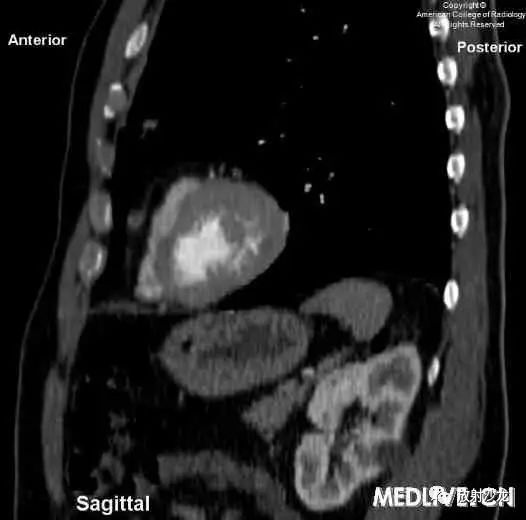

图1和图2:轴位和矢状位的CT增强扫描显示,左前外侧心包腔可见一约8毫米的低密度灶,并可见高密度包膜。矢状位图像表明,这一病变明显与任何膈肌病变无关,因此膈疝是不可能的。